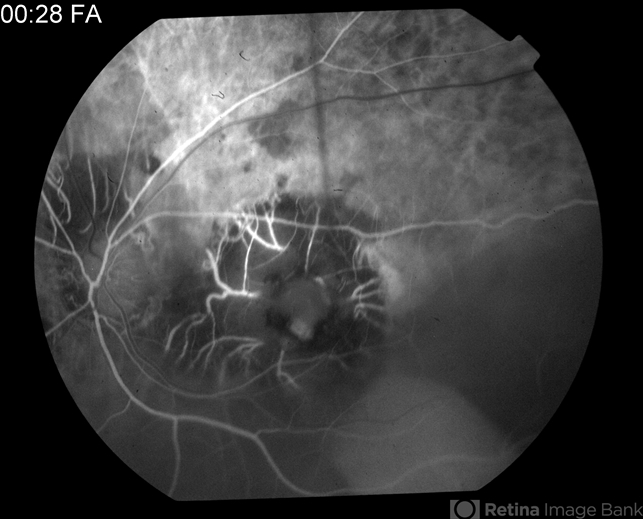

- tuberculosis, macular scar

- 0:28 second FA of 81-year-old male - old tuberculosis scar.